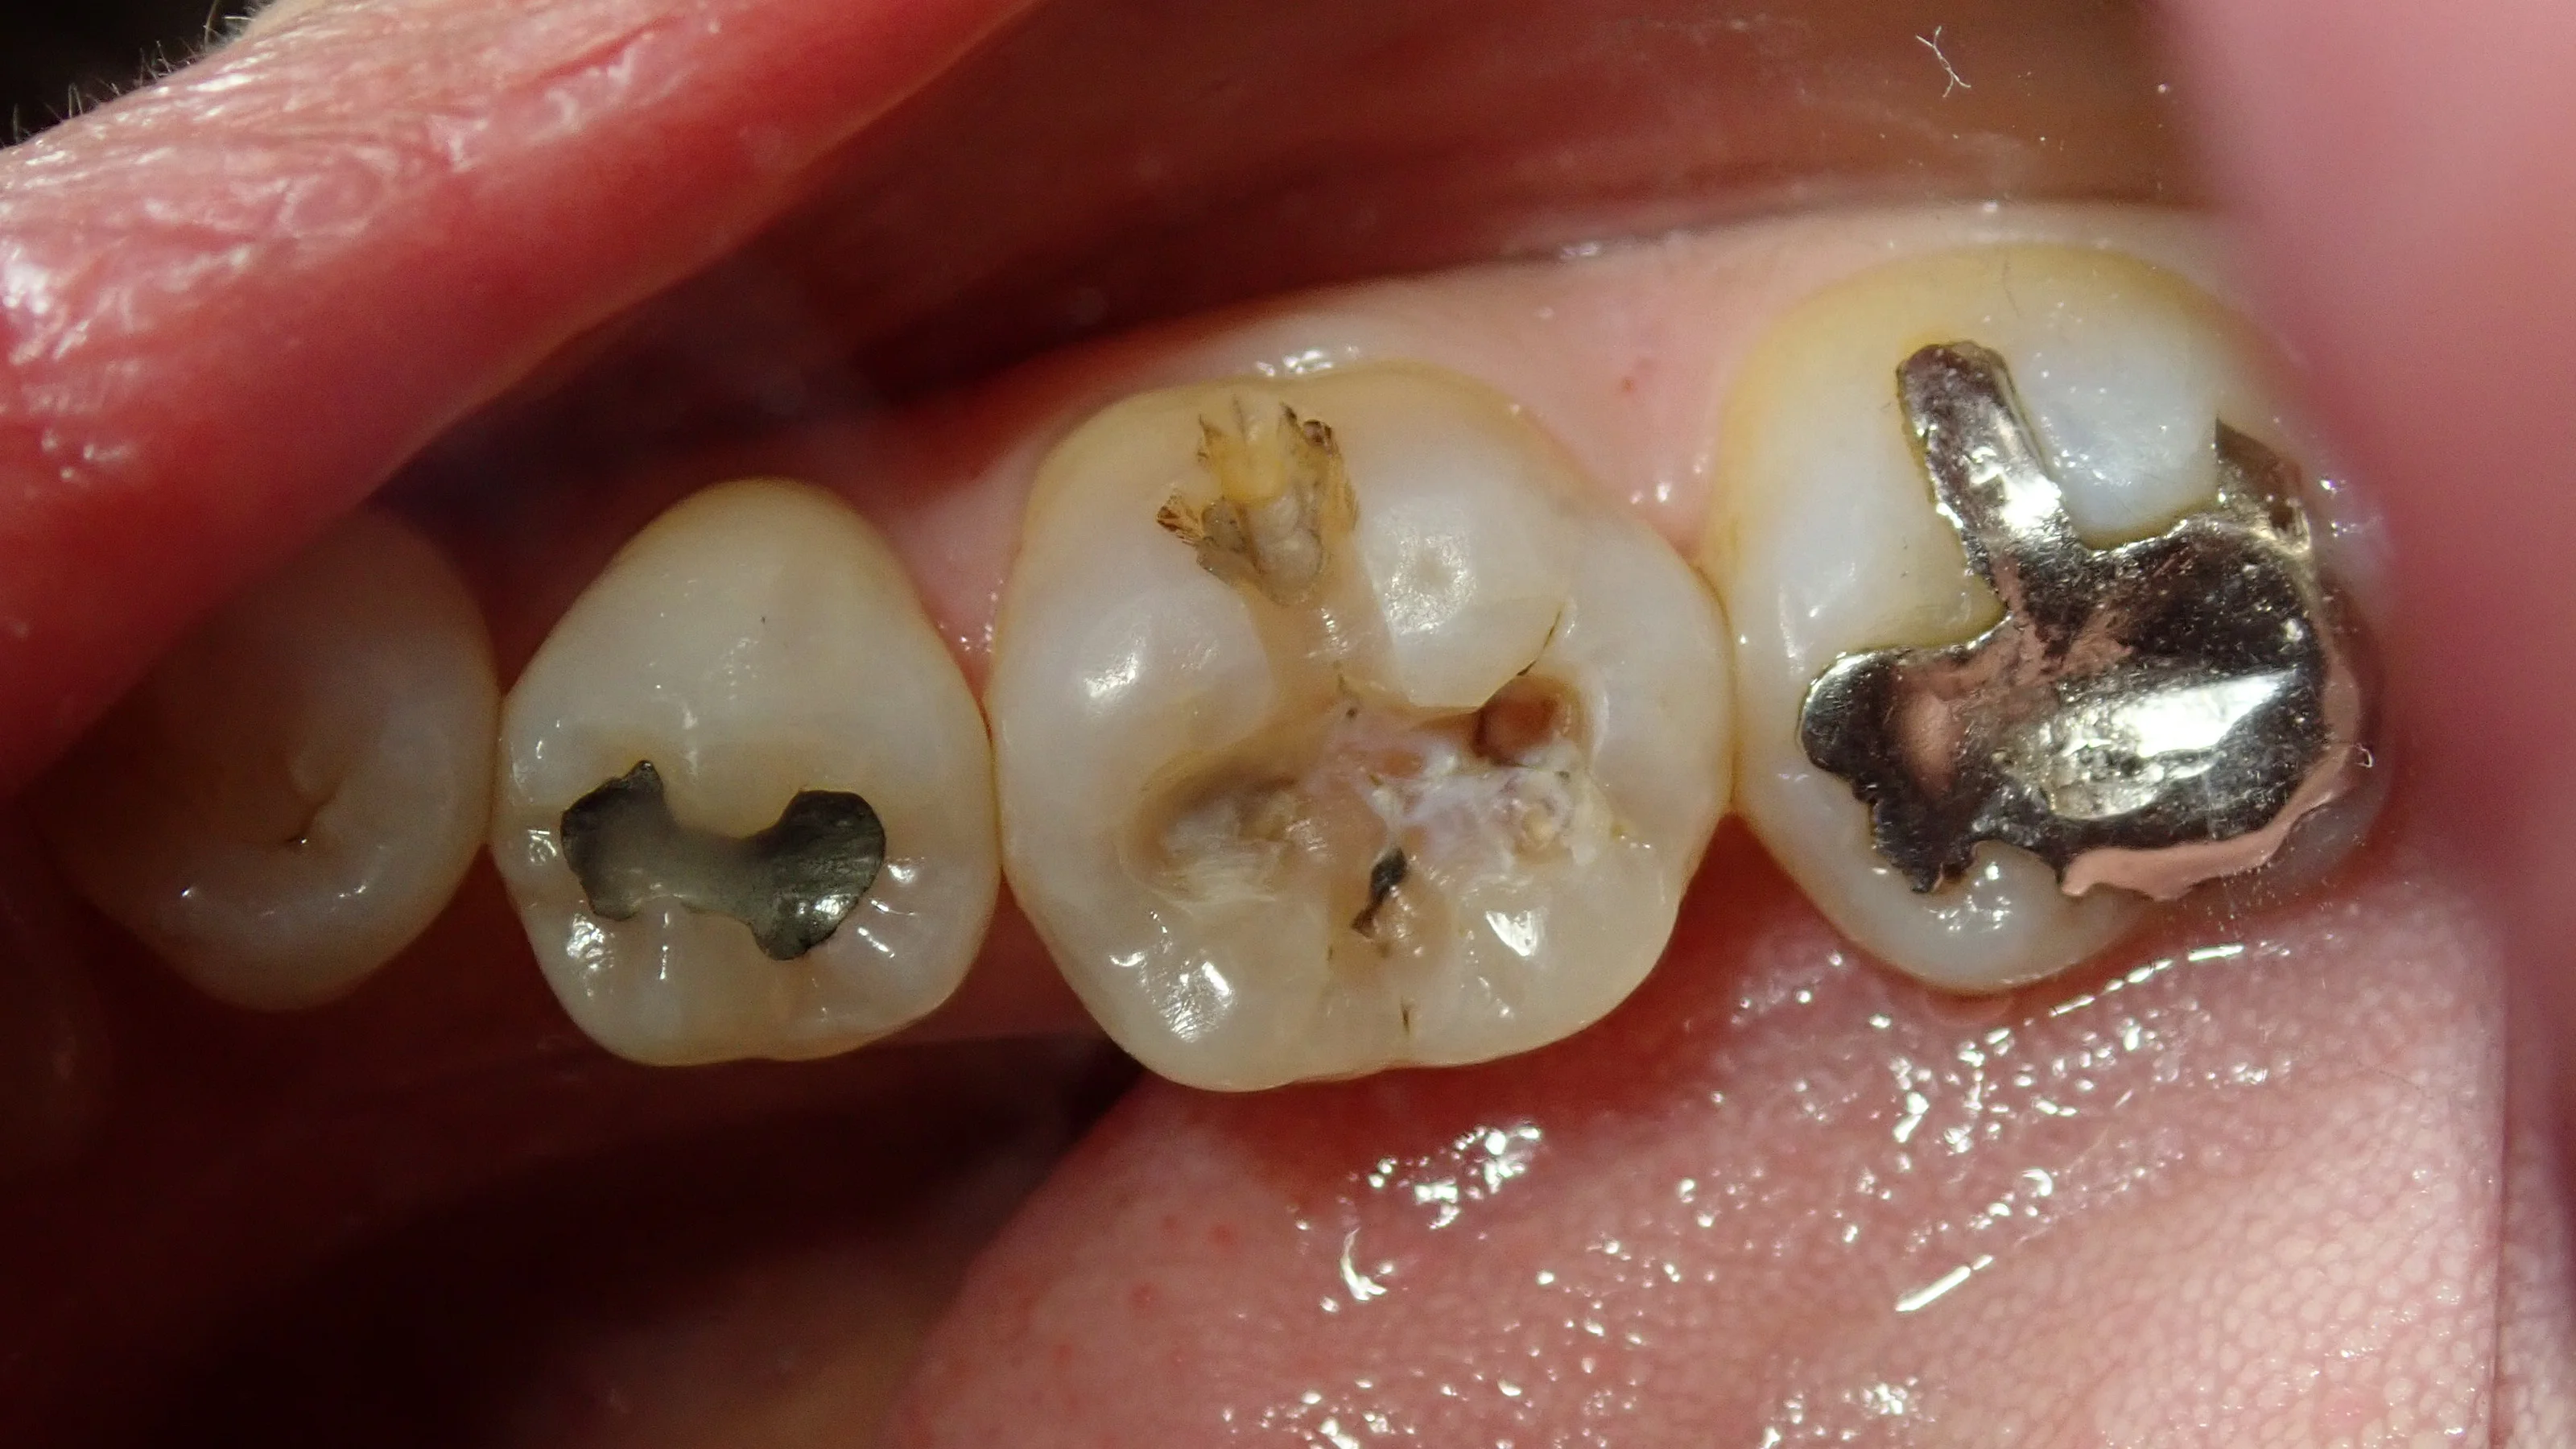

術後の写真がこちらです。

コンポジットレジン|坂寄歯科医院(取手市藤代) - 画像4

やはりダイレクトボンディングのように裂溝(歯の溝)をステイン(着色剤)で着色して作るわけではないので、不自然な仕上がりになりますね。

(とはいっても、一般の方が遠めに見る分には気付かれないとは思いますが・・・)

術前術後の比較がこちらです。

コンポジットレジン|坂寄歯科医院(取手市藤代) - 画像5

元々最初に書いた通り、コンポジットレジンで治療されていたのですが、保険制度というものは左のように平坦な感じに詰めても、今回私が詰めたように段差を再現して詰めても同じ金額になります。

どちらが良いというわけではありませんが・・・

少なくとも私は自分で治療されるのであればある程度の形態の回復はして頂きたいと思いますので、いつもこんな感じで段差を付けて治しています。